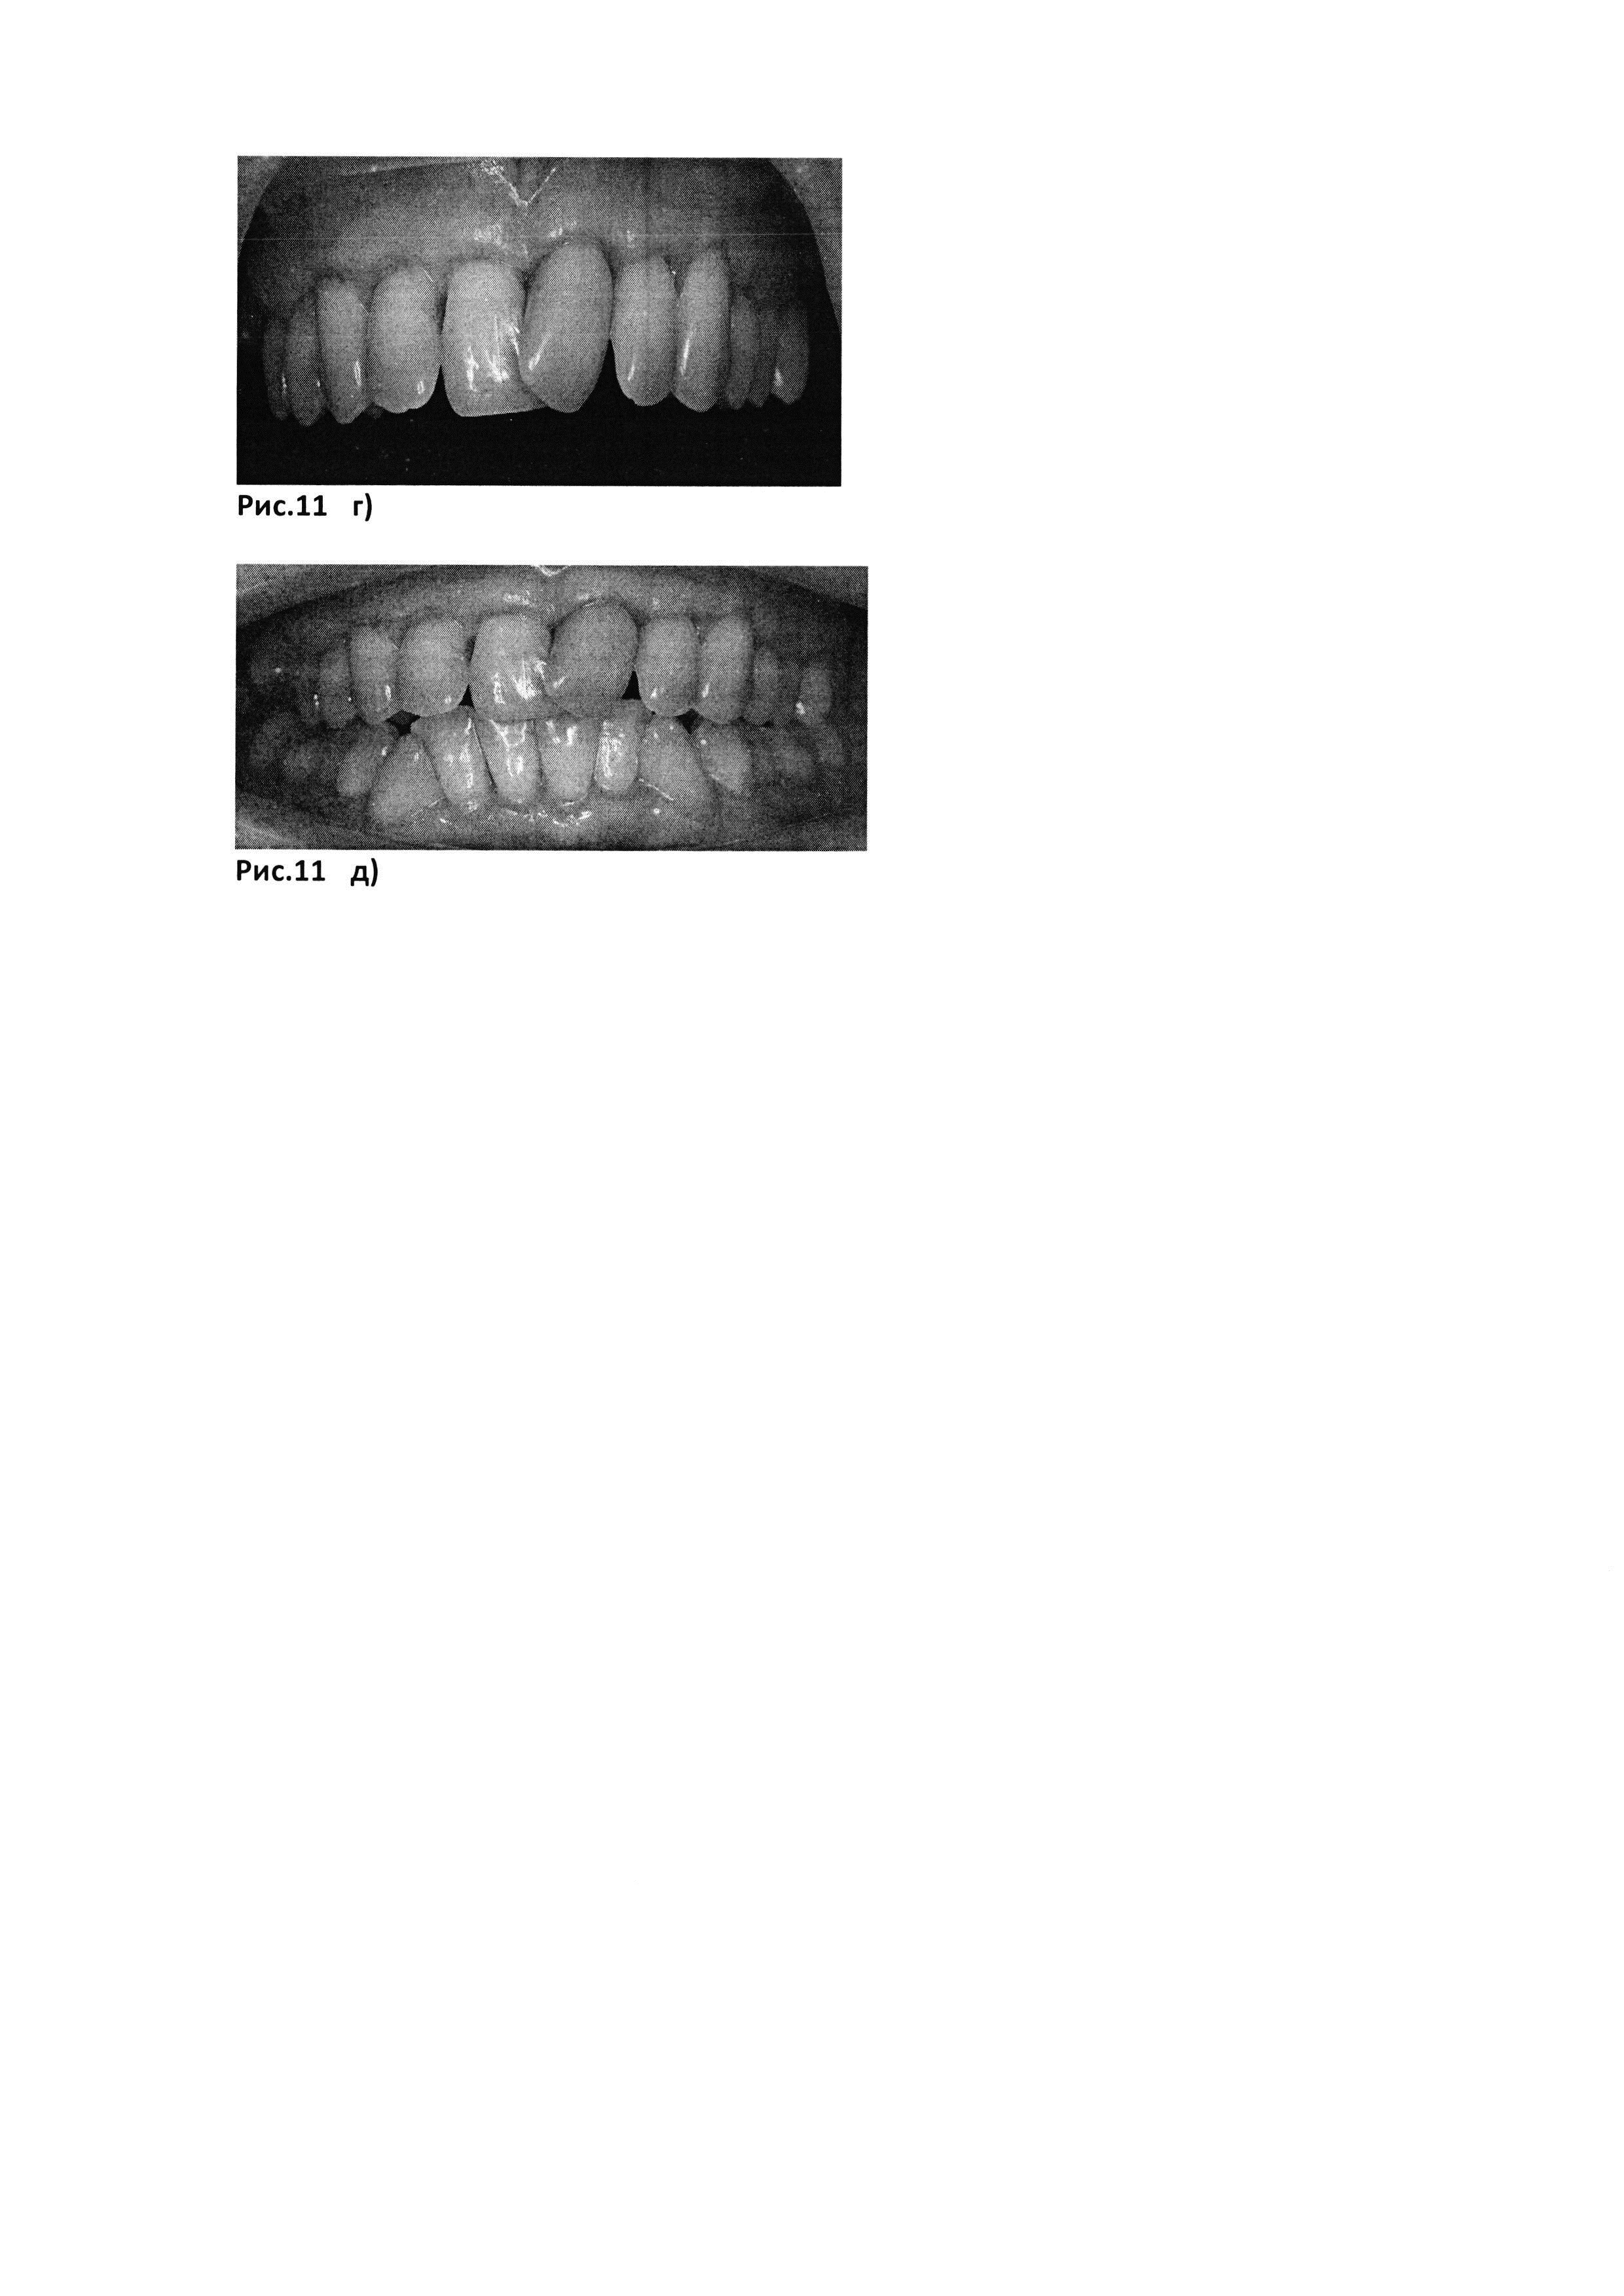

[45]

Рис. 9. е) через 3 месяца после операции

[46]

Рис. 9. ж) через 6 месяцев после операции

[47]

Рис. 10. б). Биотрансплантаты, представляющие собой PRF-мембраны (полученные с помощью центрифуги Scilogex, USA (РУ №РЗН 2015/3442) с интегрированными в них аутоФС пациента.

[48]

Рис. 10. а) до лечения

[49]

Рис. 10. в) сразу после операции

[50]

Рис. 10. г) через 12 дней после операции

[51]

Рис. 10. д) через месяц после операции